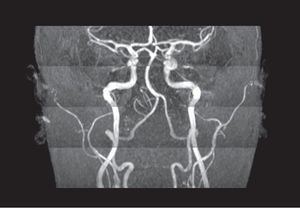

QUIZ!!! 3D TOF MRA. What is the name of this artifact? How can we avoid it?